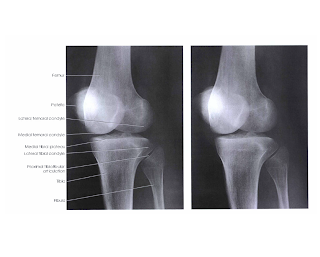

Gambar IIC.3 Gambar Radiograf Antero Posterior Knee Joint Normal (CLARK, 2005)

1)      Struktur yang terlihat

a)      Distal femur dan proksimal tibia dan fibula terlihat

b)      Ruang femorotibial joint terbuka, dengan articular facets tibia terlihat di akhir dengan visualisasi area permukaan yang minimalis.

2)      Posisi

a)      Tidak ada rotasi dibuktikan dengan tibial condyles dan ruang sendinya simetris.

b)      Kira-kira setengah dari pertengahan caput fibula superposisi dengan tibia.

c)      Intercondylar eminence terlihat di pertengahan intercondylar fossa.

3)      Kolimasi dan CR

a)      Lapangan kolimasi lurus dengan poros panjang IR.

b)      Pertengahan lapangan kolimasi berada di pertengahan knee joint.

4)      Kriteria eksposi

a)      Eksposi yang optimal akan menampakkan garis tepi patella pada sistal femur, dan caput fibula dan leher fibula tidak terlihat overeksposi.

b)      Tidak ada pergerakan, trabekula tulang tampak dan tajam

c)      Tampak soft tissue